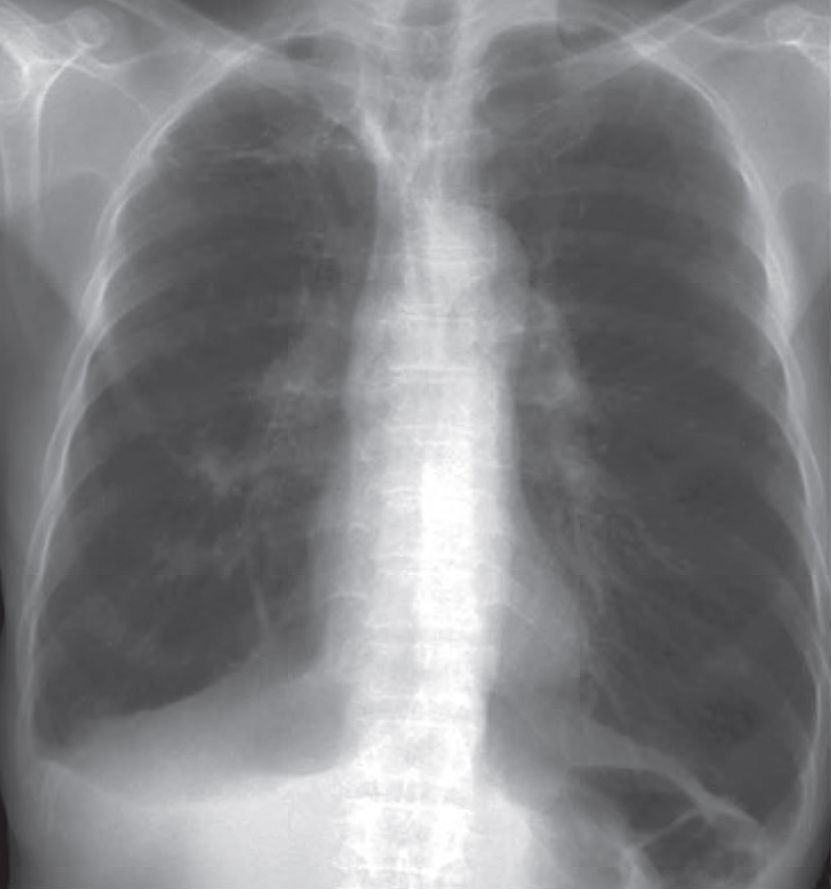

A 70-year-old chronic smoker for 50 years presented with exertional shortness of breath for 1 year. His exercise tolerance was limited to 1 flight of stairs and he remained largely home-bound for recent 6 months.

Physical examination showed he was tachypnoeic with central cyanosis. Examination of respiratory system revealed use of accessory muscles of respiration and hyperinflated chest on both sides.

What abnormality can you identify on CXR and what’s the likely diagnosis ?